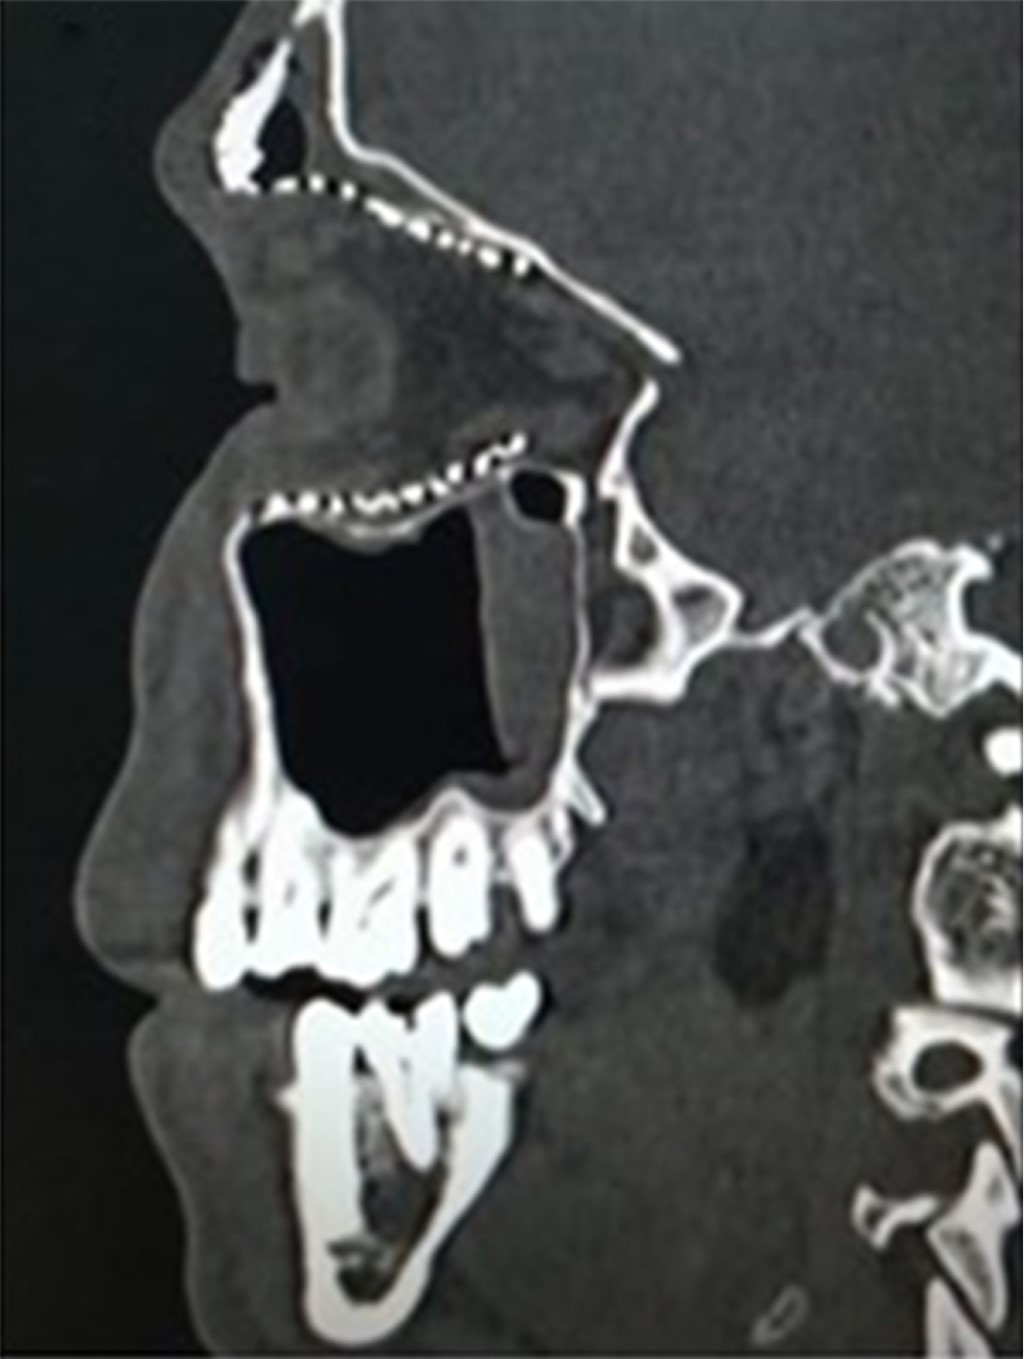

La tomografía computarizada coronal de la cara muestra una extensa destrucción de la pared orbital medial (Figura 5) y la reconstrucción con malla de titanio para corregir el extenso defecto (Figura 6).

La tomografía de la cara muestra afectación de la pared orbital medial que a su vez afecta al suelo orbital y a la región de la zona clave (Figura 9).